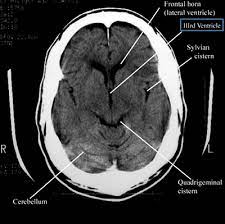

A head CT scan is a non-invasive imaging procedure that provides detailed images of the brain and skull. It is particularly useful in diagnosing conditions such as tumors, internal injuries, and other abnormalities that might not be visible through a regular X-ray. For Reema, this scan represented a beacon of hope, a chance to confront her fears and find a resolution.